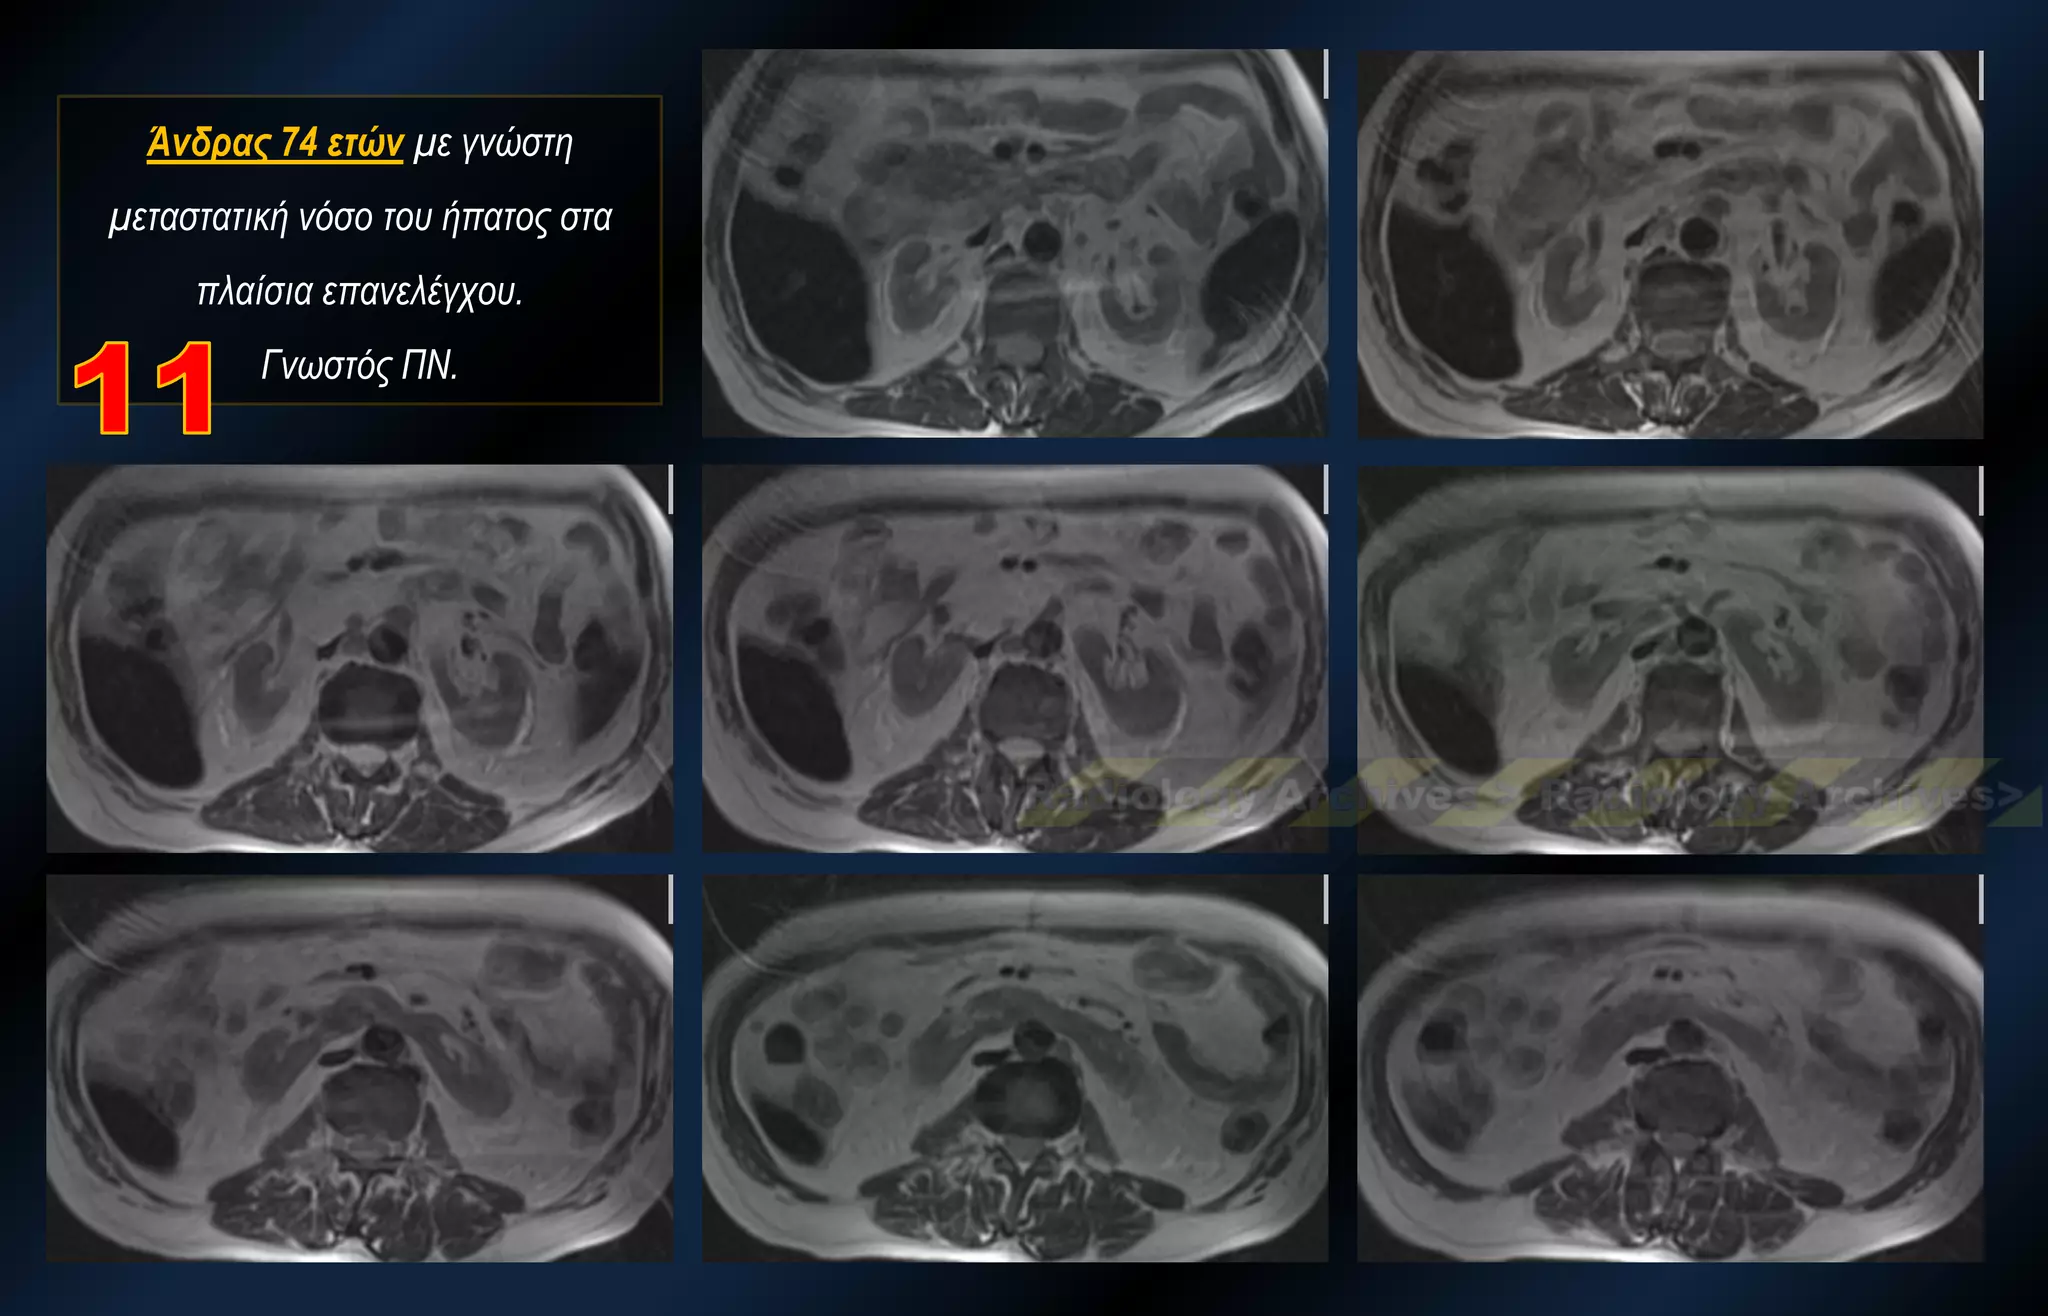

Άνδρας 74 ετών με γνώστη μεταστατική νόσο του ήπατος στα πλαίσια επανελέγχου. Γνωστός ΠΝ.

Άνδρας 74 ετώνμε γνώστη μεταστατική νόσο του ήπατος στα πλαίσια επανελέγχου. Γνωστός ΠΝ.